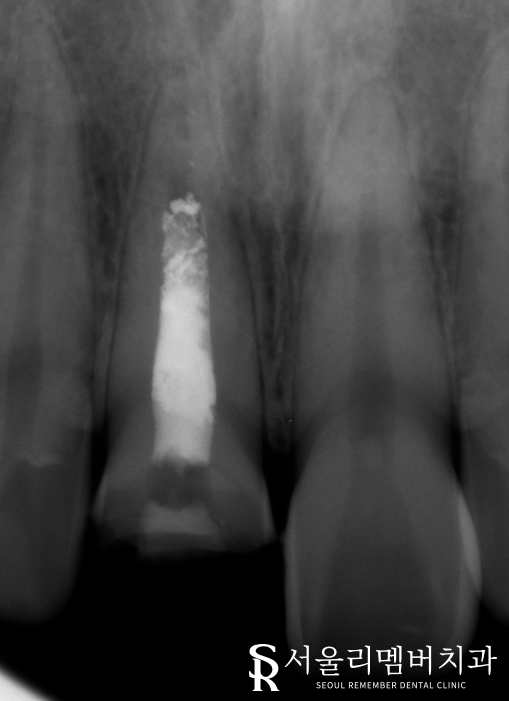

치아상태를 확인하기 위해 Panorama 촬영을 하였고,

좀 더 자세히 보기 위해

Standard x-ray를 추가로 찍었습니다.

사진을 보시면 치아 머리(치관)부위가 부러져있고

뿌리쪽 흰색으로 되어 있는 부분은

과거에 신경치료를 받은 상태였습니다.